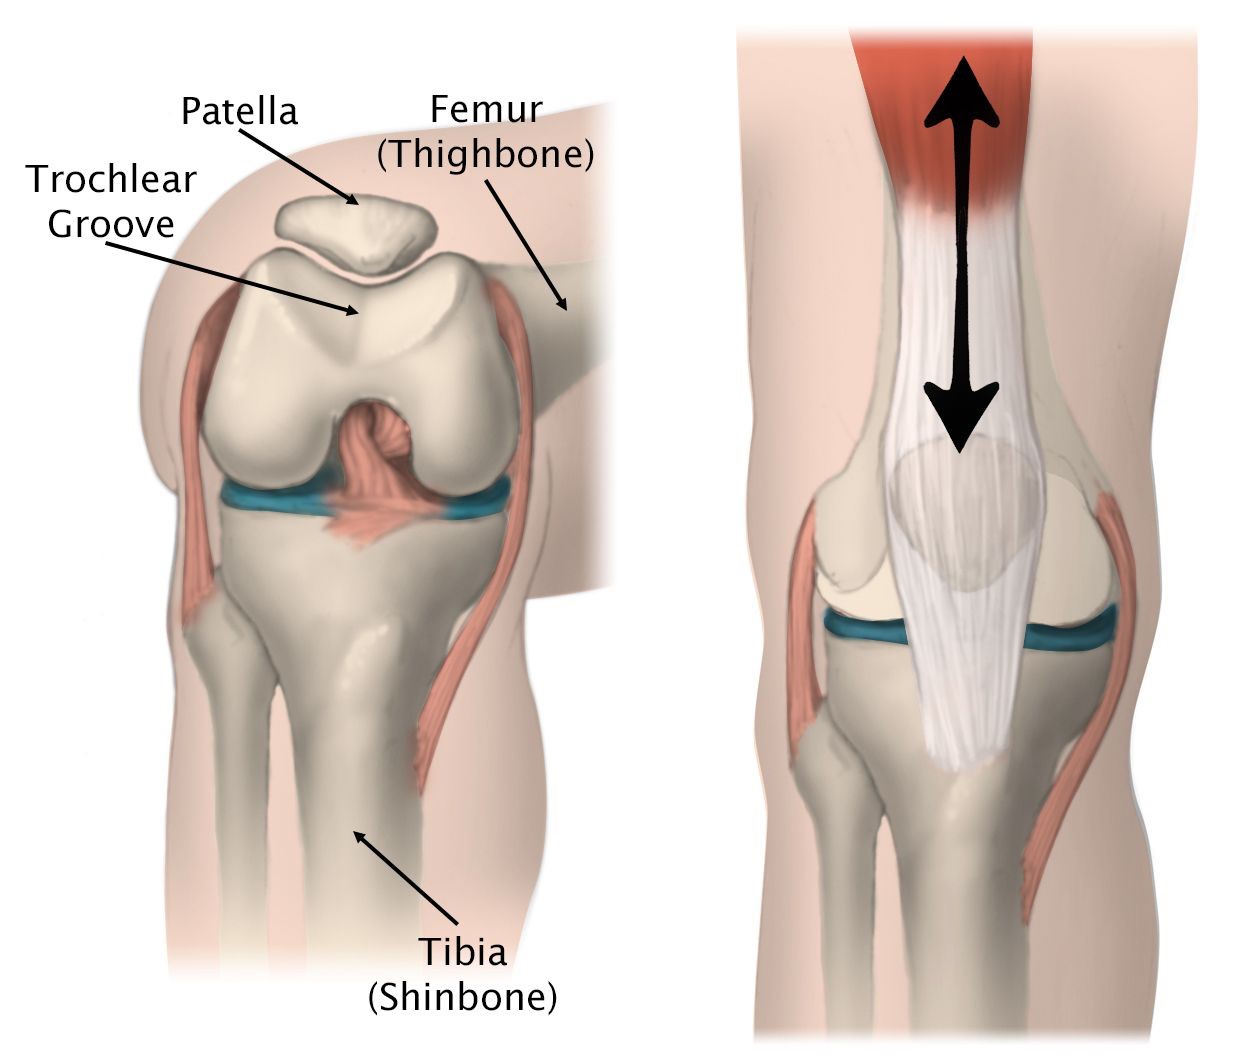

Within the patellofemoral compartment, the patella lies in a groove on the top of the femur called the trochlea. When you bend or straighten your knee, the patella moves up and down within this trochlear groove. Articular cartilage covers the ends of the femur, trochlear groove, the underside of the patella, and the upper surface of the tibia, and this allows movement of the joint.

An incision is made over the front of the knee incorporating the knee arthroscopy wound, and the distal femur and patella are exposed. The wound is smaller than the normal incision for total knee replacement. Specialized surgical guides are used to remove the worn-out surface under the patella and to shape the trochlear groove of the femur. The metal component, similar in size and shape to the end of the femur, is cemented to the bone. and the patellar button is also cemented.

Once the components are inserted, the knee is moved along the range of motion to confirm the accurate positioning and tracking of the implants. The wound is closed in layers over a suction drain. The operation takes about 60-90 minutes to complete. A/Prof Woodgate utilises the RBK Patellofemoral Joint System for this procedure.